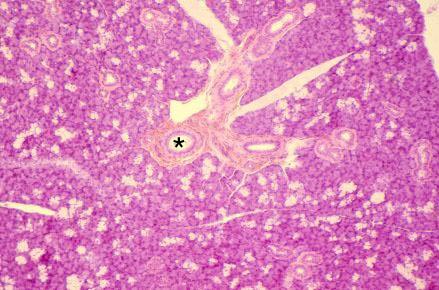

VIII-17, Slide 51, Submandibular Gland (H&E). The submandibular gland is a mixed gland, with basophilic serous acini more numerous than clear-staining mucous tubules. Note the interlobular duct (*).